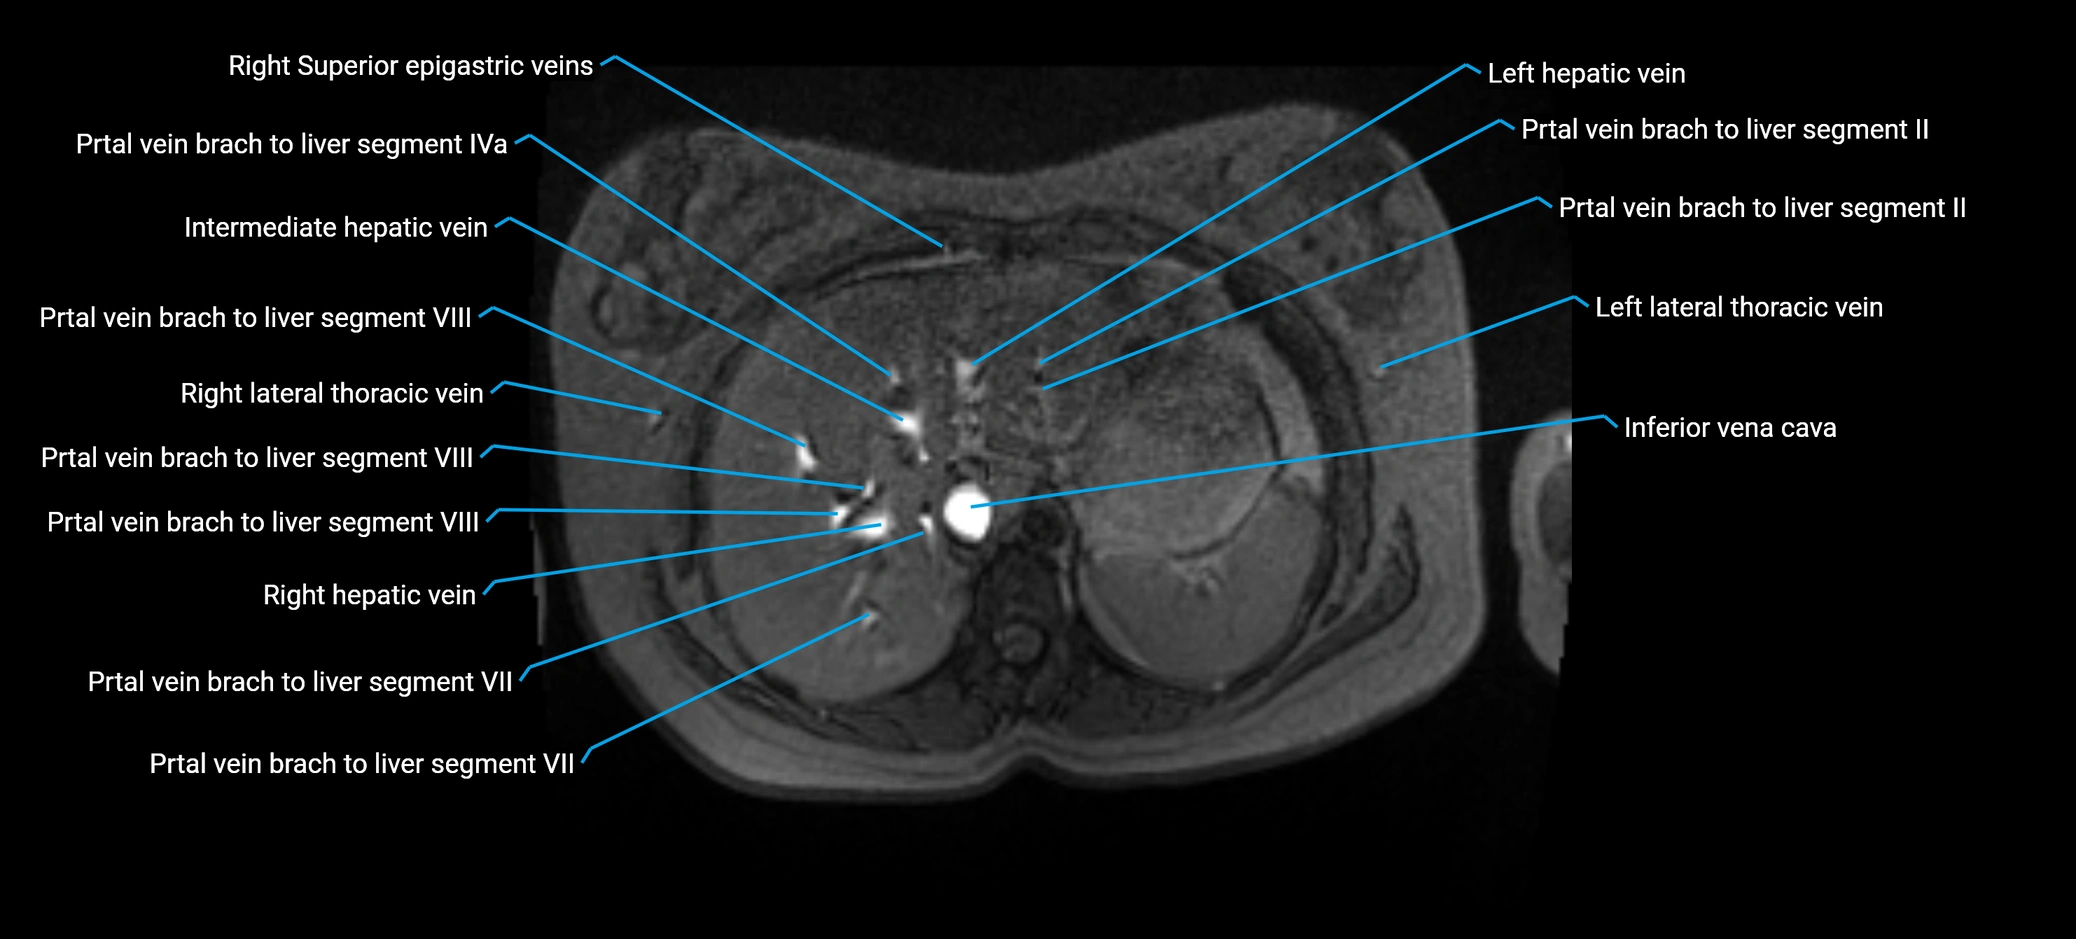

MRI image

image